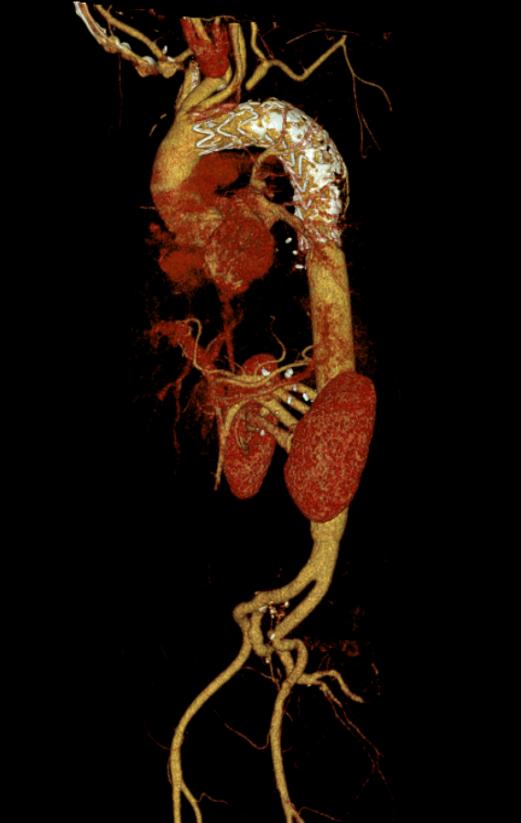

11月15日凌晨1时许,该患者因突发腰背部剧烈疼痛到我院紧急就诊。据了解,该患者10年前曾因胸主动脉夹层接受胸主动脉腔内修复术,院外增强CT检查提示胸腹主动脉瘤,病变最危险部位的血管直径已扩张至7.5cm,且血液正持续从破口渗出,这颗藏于患者体内的“不定时炸弹”一旦彻底破裂,将引发致命性大出血,患者生命危在旦夕。

面对挑战,赖应龙教授团队邀请首都医科大学朱俊明教授团队胡海瓯教授,联合我院麻醉科、手术中心、体外循环及重症监护团队参与救治,并进行了详尽的术前模拟与预案推演,为患者量身定制了周密的手术方案。在12个小时的紧张手术中,多学科团队采用了顶尖的“深低温停循环”技术,为精细操作创造了宝贵的时间窗口,病变的主动脉被成功替换为人工血管,所有重要分支血管均实现精准吻合。术后,患者生命体征平稳转入该科重症监护室进一步治疗,经过10余天的精准救治与精心护理,患者饮食睡眠、肝功能、肾功能、心脏功能及凝血功能显著好转,顺利出院。

胸腹主动脉瘤破裂属于致死率极高的急症,而胸腹主动脉联合替换+双侧髂动脉替换术因需同时处理胸、腹、髂三段血管,涉及多器官供血保护、复杂血管吻合与大出血防控,对医疗团队的技术精度、应急能力和多学科协作水平要求近乎苛刻,素有外科领域“珠穆朗玛峰”之称。此次手术的成功突破,彰显了科室在高难度复杂手术中的硬核实力与综合诊疗水平。